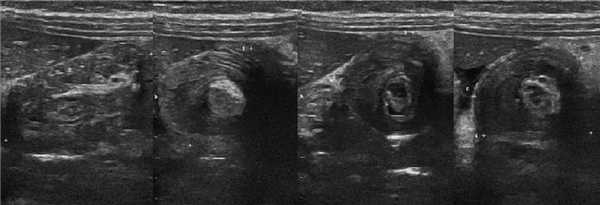

Рисунок. Мальчик в возрасте 6-ти месяцев поступил в больницу с болью в животе, рвотой и кровавыми испражнениями. На УЗИ под печенью определяется цилиндрическое слоистое образование (длина 40 мм, диаметр 30 мм) и небольшое количество свободной жидкости (4). Заключение: Эхо-признаки инвагинации кишечника.

Рисунок. Мальчик 4-х лет с жалобами на внезапную сильную боль в животе. Внизу живота справа определяется слоистая цилиндрическая масса, в структуре которой хорошо видно гиперэхогенный жир брыжейки с округлыми гипоэхогенными лимфоузлами. Заключение: Эхо-признаки инвагинации кишечника.